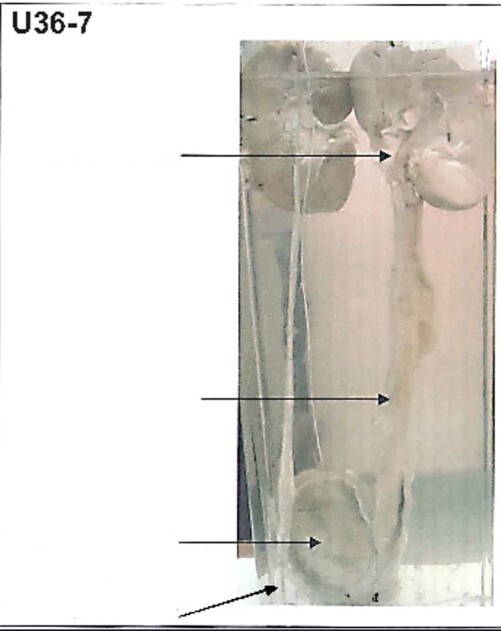

What is the specimen?

Gross pathology